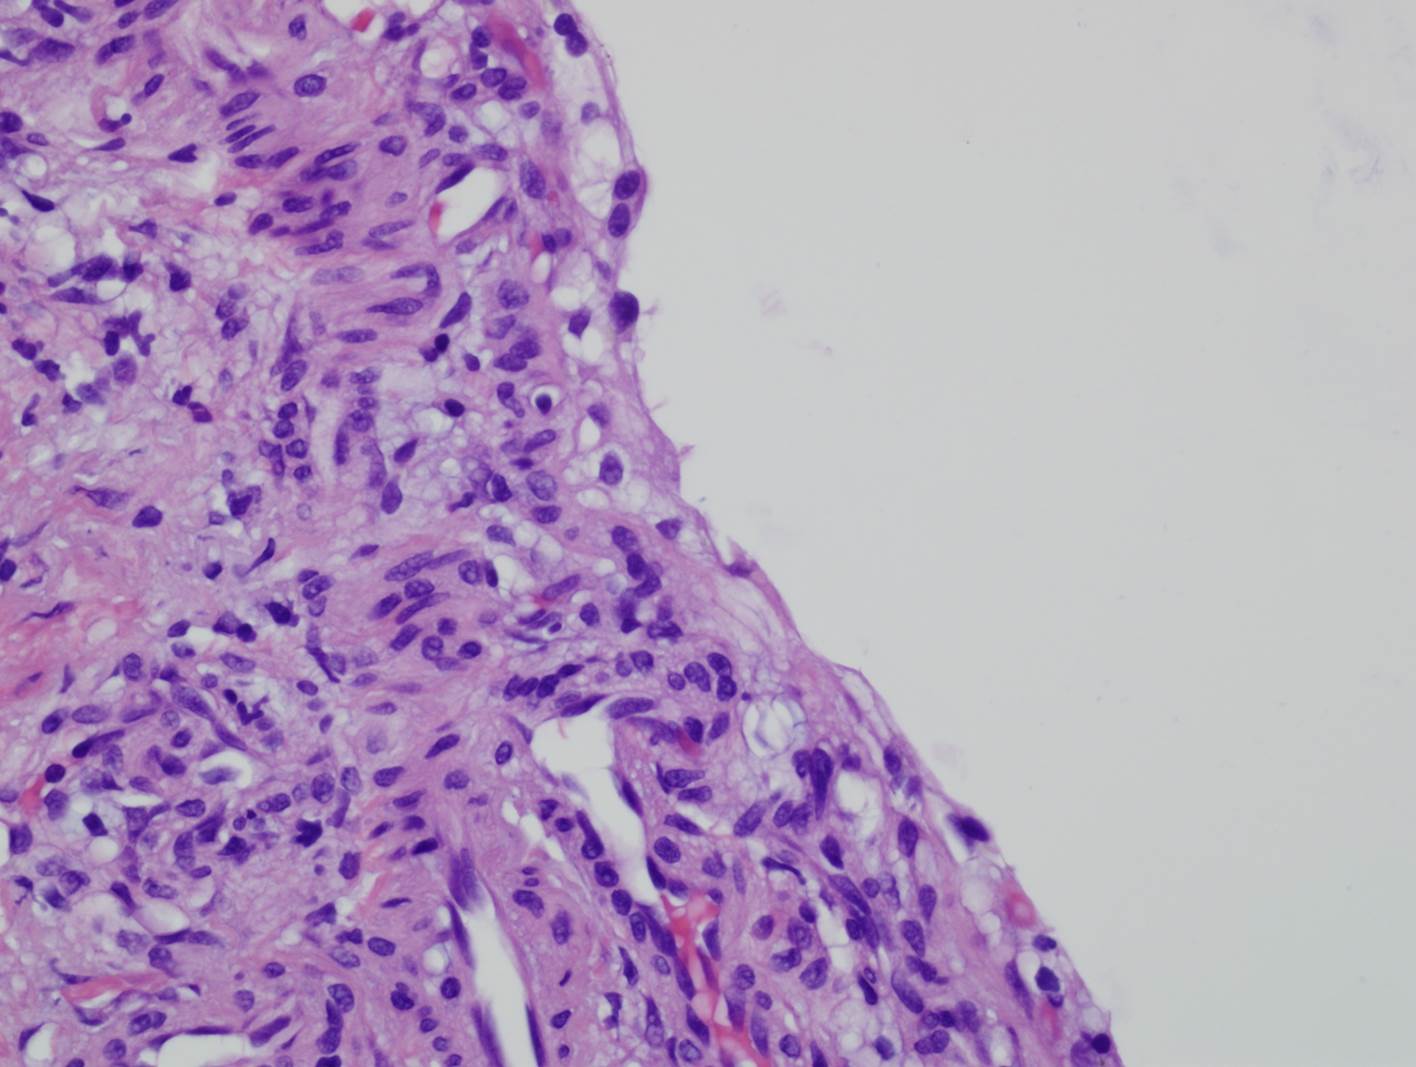

Classification of renal tumors

Case ID: 809